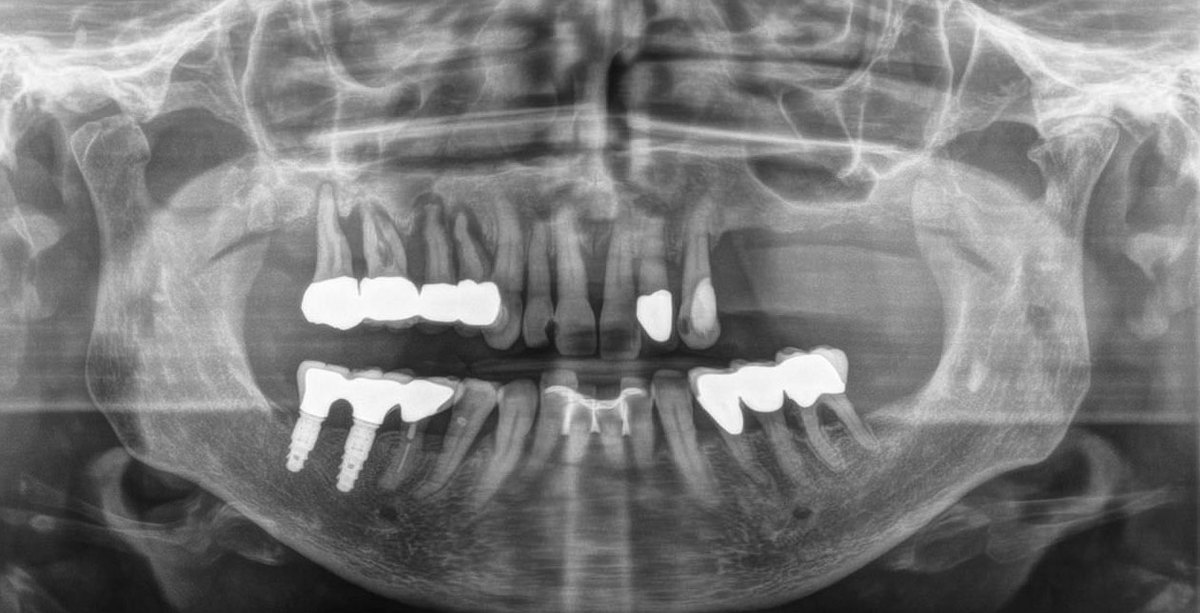

Dental health relies heavily on accurate, detailed imaging for diagnosis and treatment planning. To address this, Panorex was developed. A Panorex image is a two-dimensional, panoramic view of the entire oral and maxillofacial region. Unlike traditional intraoral X-rays focusing on specific teeth, the Panorex captures a broader perspective, providing a comprehensive view of the jaws, teeth, and surrounding structures. At MountainView Dental, it is a valuable diagnostic tool we use for various dental and maxillofacial applications.

One of the primary benefits of Panorex imaging in Hurricane, UT, is its ability to capture a comprehensive view of the entire oral and maxillofacial region in a single image. This includes the upper and lower jaws, teeth, temporomandibular joints (TMJ), sinuses, and adjacent structures. Such a broad perspective aids in the early detection of various dental and maxillofacial abnormalities, providing a holistic understanding of a patient's oral health.